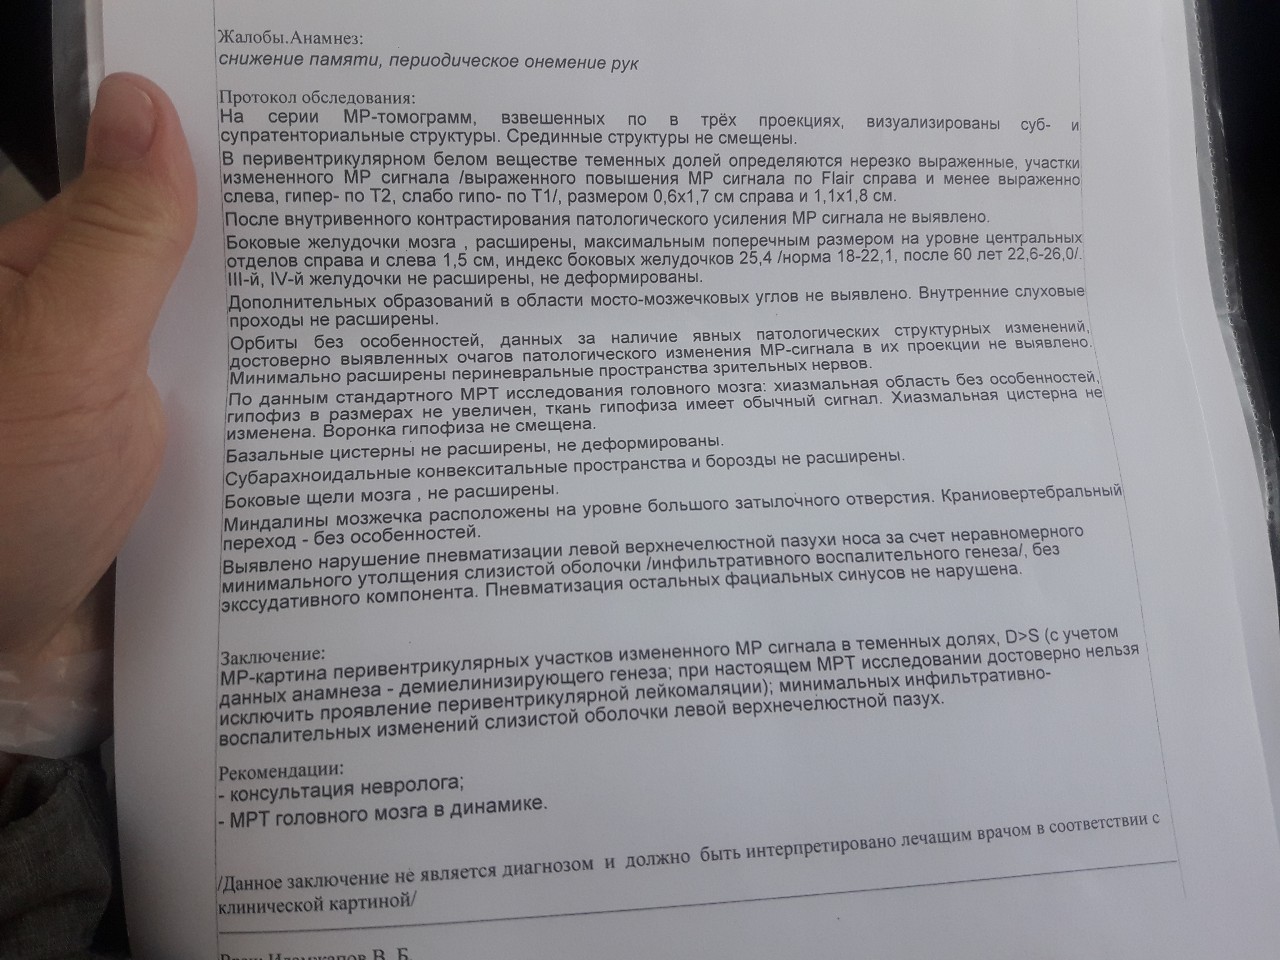

МРТ головного мозга: Расшифровка снимков и Интерпретация

Раздел: Визуальные уроки